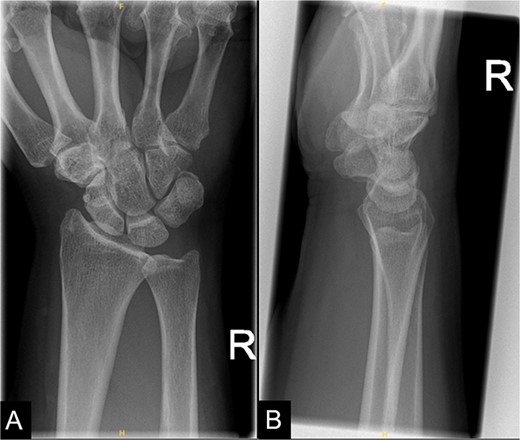

On examination of the right wrist, the patient had a palpable, tender lump in the region of the flexor carpi radialis tendon at the level of the distal radius. There was no associated erythema. Given the pain, the patient had a reduced range of movement during volar flexion of the wrist. There were no abnormalities during a neurovascular examination. Blood investigations were all unremarkable. An X-ray of the right wrist confirmed calcification at the flexor carpi radialis level at the wrist (Fig. 1).

An X-ray of the right wrist which shows calcification at the level of flexor carpi radialis at the wrist.